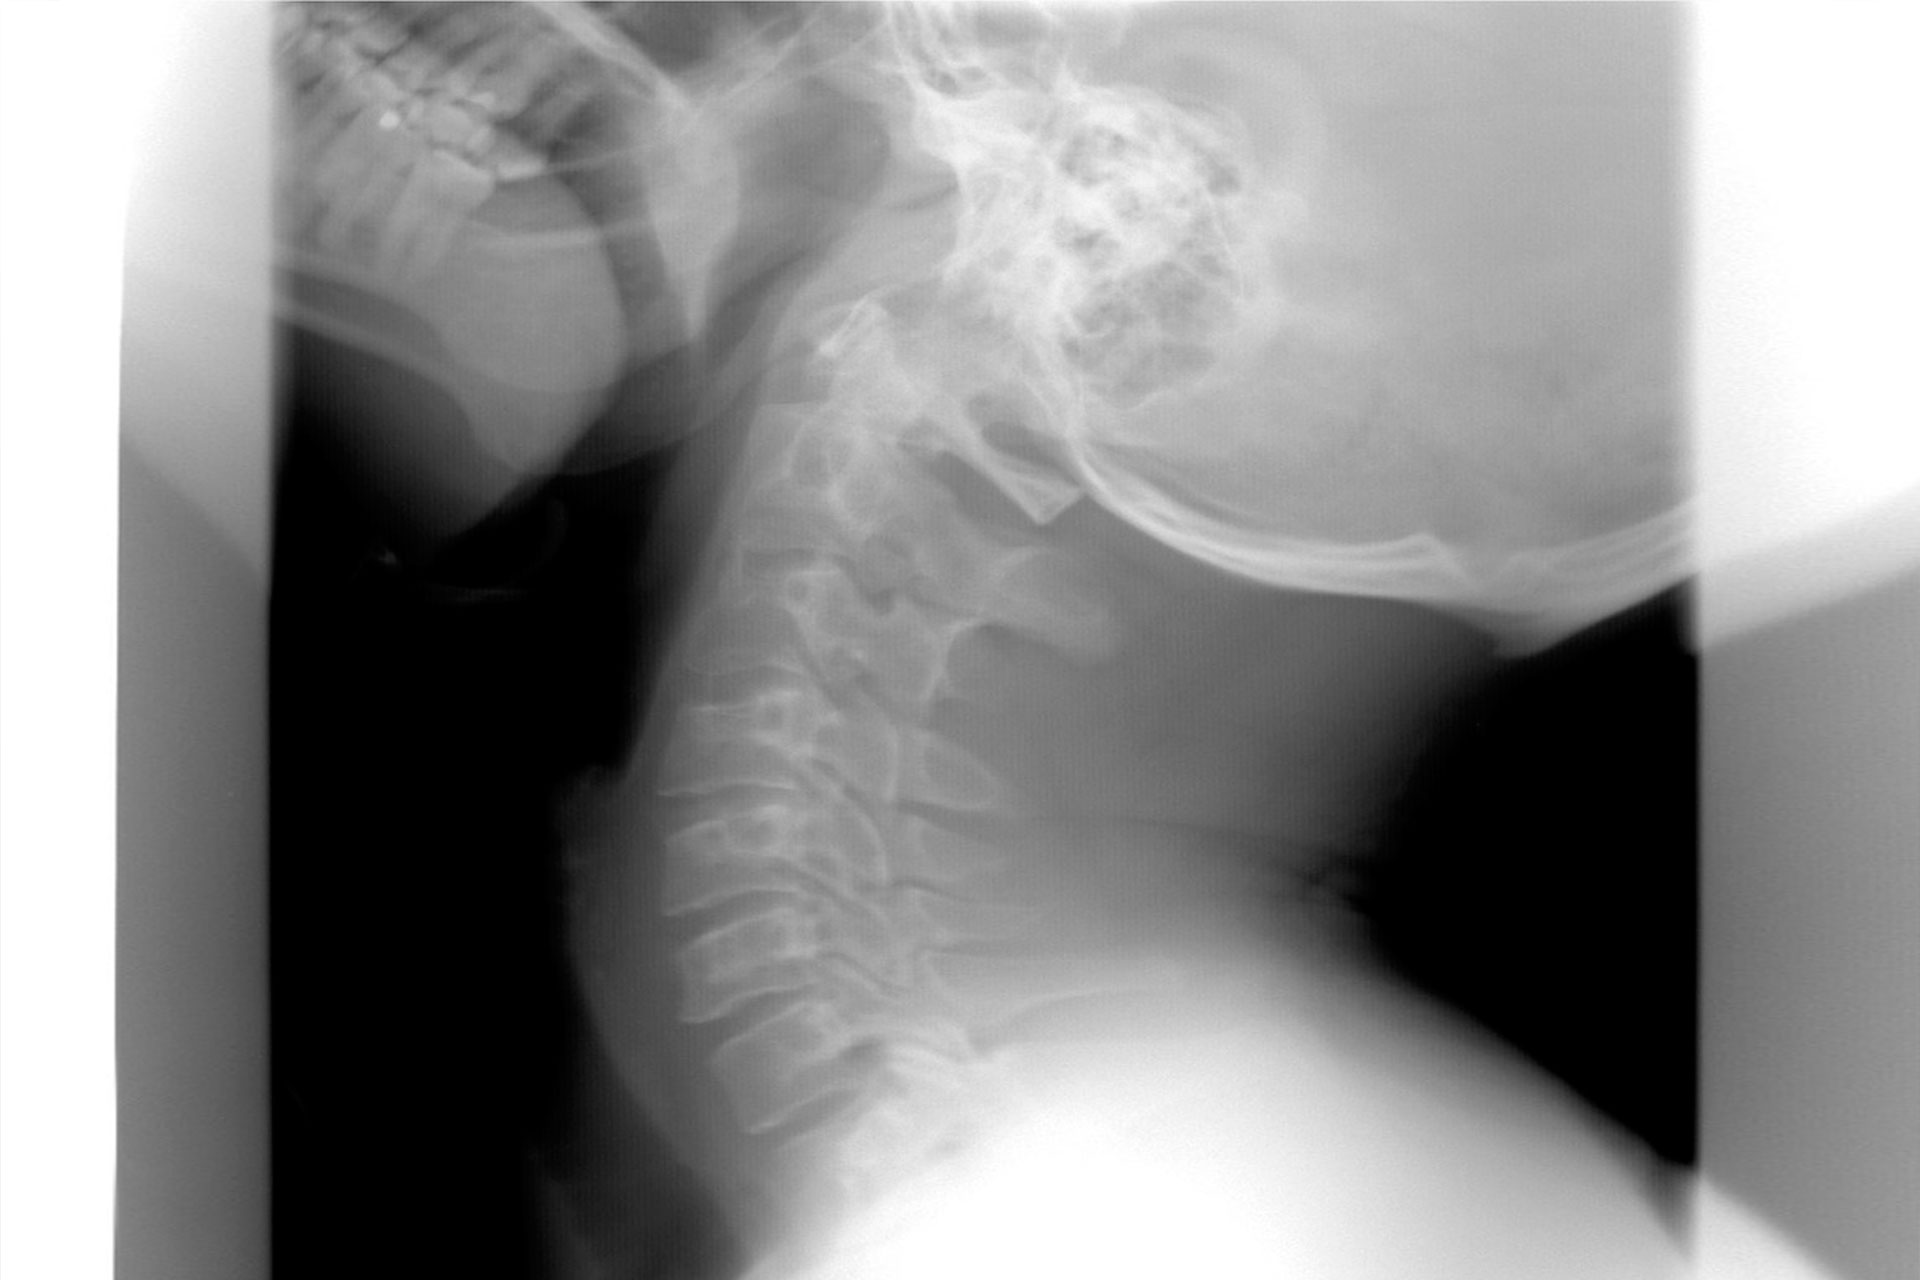

El latigazo cervical es una de las lesiones más frecuentes en los accidentes de tráfico. Podemos definirla como aquella que se produce en el cuello como consecuencia de una extensión brusca provocada por el impacto. El latigazo cervical afecta principalmente a la musculatura del cuello, y desencadena una serie de síntomas como dolor, mareos, vértigos, cefaleas, náuseas o vómitos, según los casos.